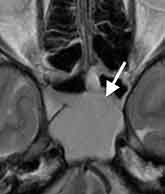

元々片頭痛のある40歳女性、突然後頭部の激痛が出現し受診。頭部MRI検査で蝶形骨洞炎を認めました。

しかし、この所見だけでは症状の説明が付かず、頭部MRA検査(脳動脈の撮像)を加えました。

後大脳動脈(後頭部から上へ行く血管)に多くの狭窄を認め、可逆性脳血管攣縮症候群と診断しました。この症例では、副鼻腔炎が誘因となり可逆性脳血管攣縮症候群を発症した可能性が考えられました。